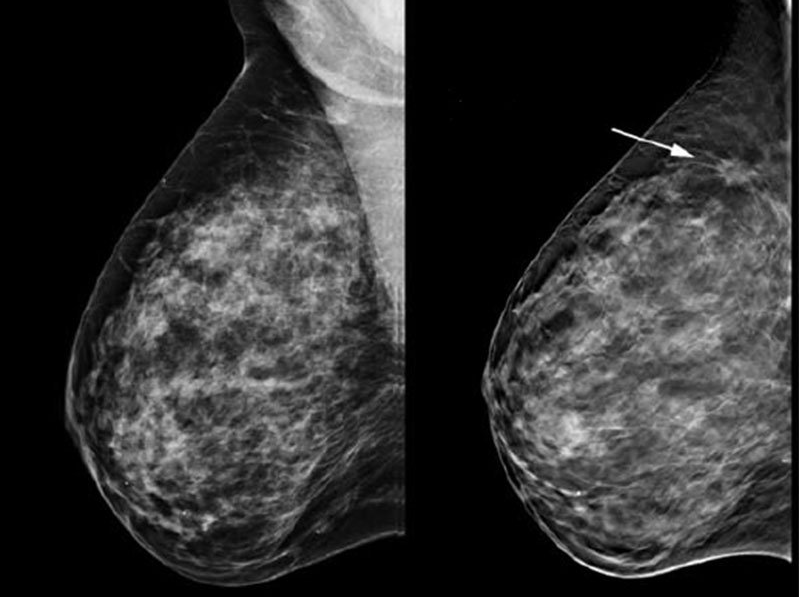

Lo studio radiologico del Dott. Famiglietti Gianfranco, specialista in radiologia diagnostica si occupa di ecotomografia, mammografia e densitometria ossea. I nostri macchinari sono tutti di ultima generazione per garantire ai nostri pazienti il miglior risultato con l'esposizione alla quantità di radiazioni più bassa possibile.

L'altissima qualità dei nostri macchinari ci permette di eseguire esami di ottima qualità in prima battuta riducendo al minimo la necessità di ripetizione e quindi ancora una volta l'esposizione del paziente a radiazioni inutili.